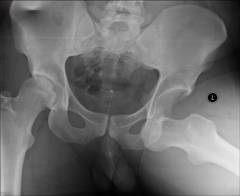

- Рентгенография. Обязательно для всех пациентов. Снимки делают в двух проекциях – спереди и сбоку.

- Рентгенография. Это исследование обязательно для всех пациентов. Снимки делают в двух проекциях – анфас и профиль, что позволяет точнее оценить положение головки бедра и выявить повреждения окружающих тканей.

- Компьютерная томография и магнитно-резонансная томография. Эти методы используются, если после рентгенографии у врача остаются сомнения в диагнозе.

Что нужно делать при вывихе тазобедренного сустава?

При вывихах бедра требуется незамедлительное оказание медицинской помощи. Сначала врач проводит клинический осмотр пациента, а затем выполняется рентгенографическое обследование таза и тазобедренных сочленений. Рентгенография позволяет наглядно оценить положение костей в суставе и исключить повреждения костной ткани.